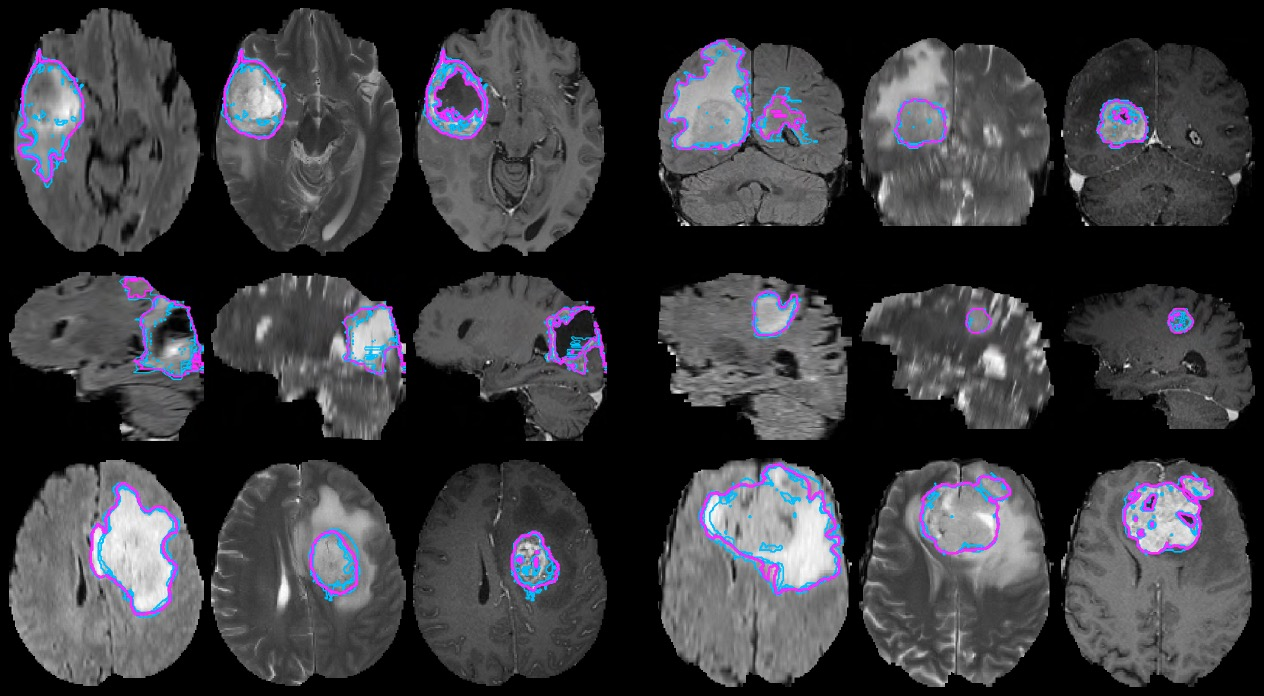

의료 영상 분석 : 의료 이미지를 분석하는 데에도 Semantic Image Segmentation 기술을 사용합니다. 예를 들어, CT 이미지나 MRI 이미지를 분석하여 악성 종양을 인식하는 데 사용될 수 있습니다. 아래 그림은 MRI로 촬영한 뇌 이미지에서 종양이 있는 부분(Brain Tumor)을 Semantic Image Segmentation 기술로 자동으로 찾아내는 예시입니다.

brain_tumor_segmentation.png Semantic Image Segmentation을 이용한 Brain Tumor Segmentation